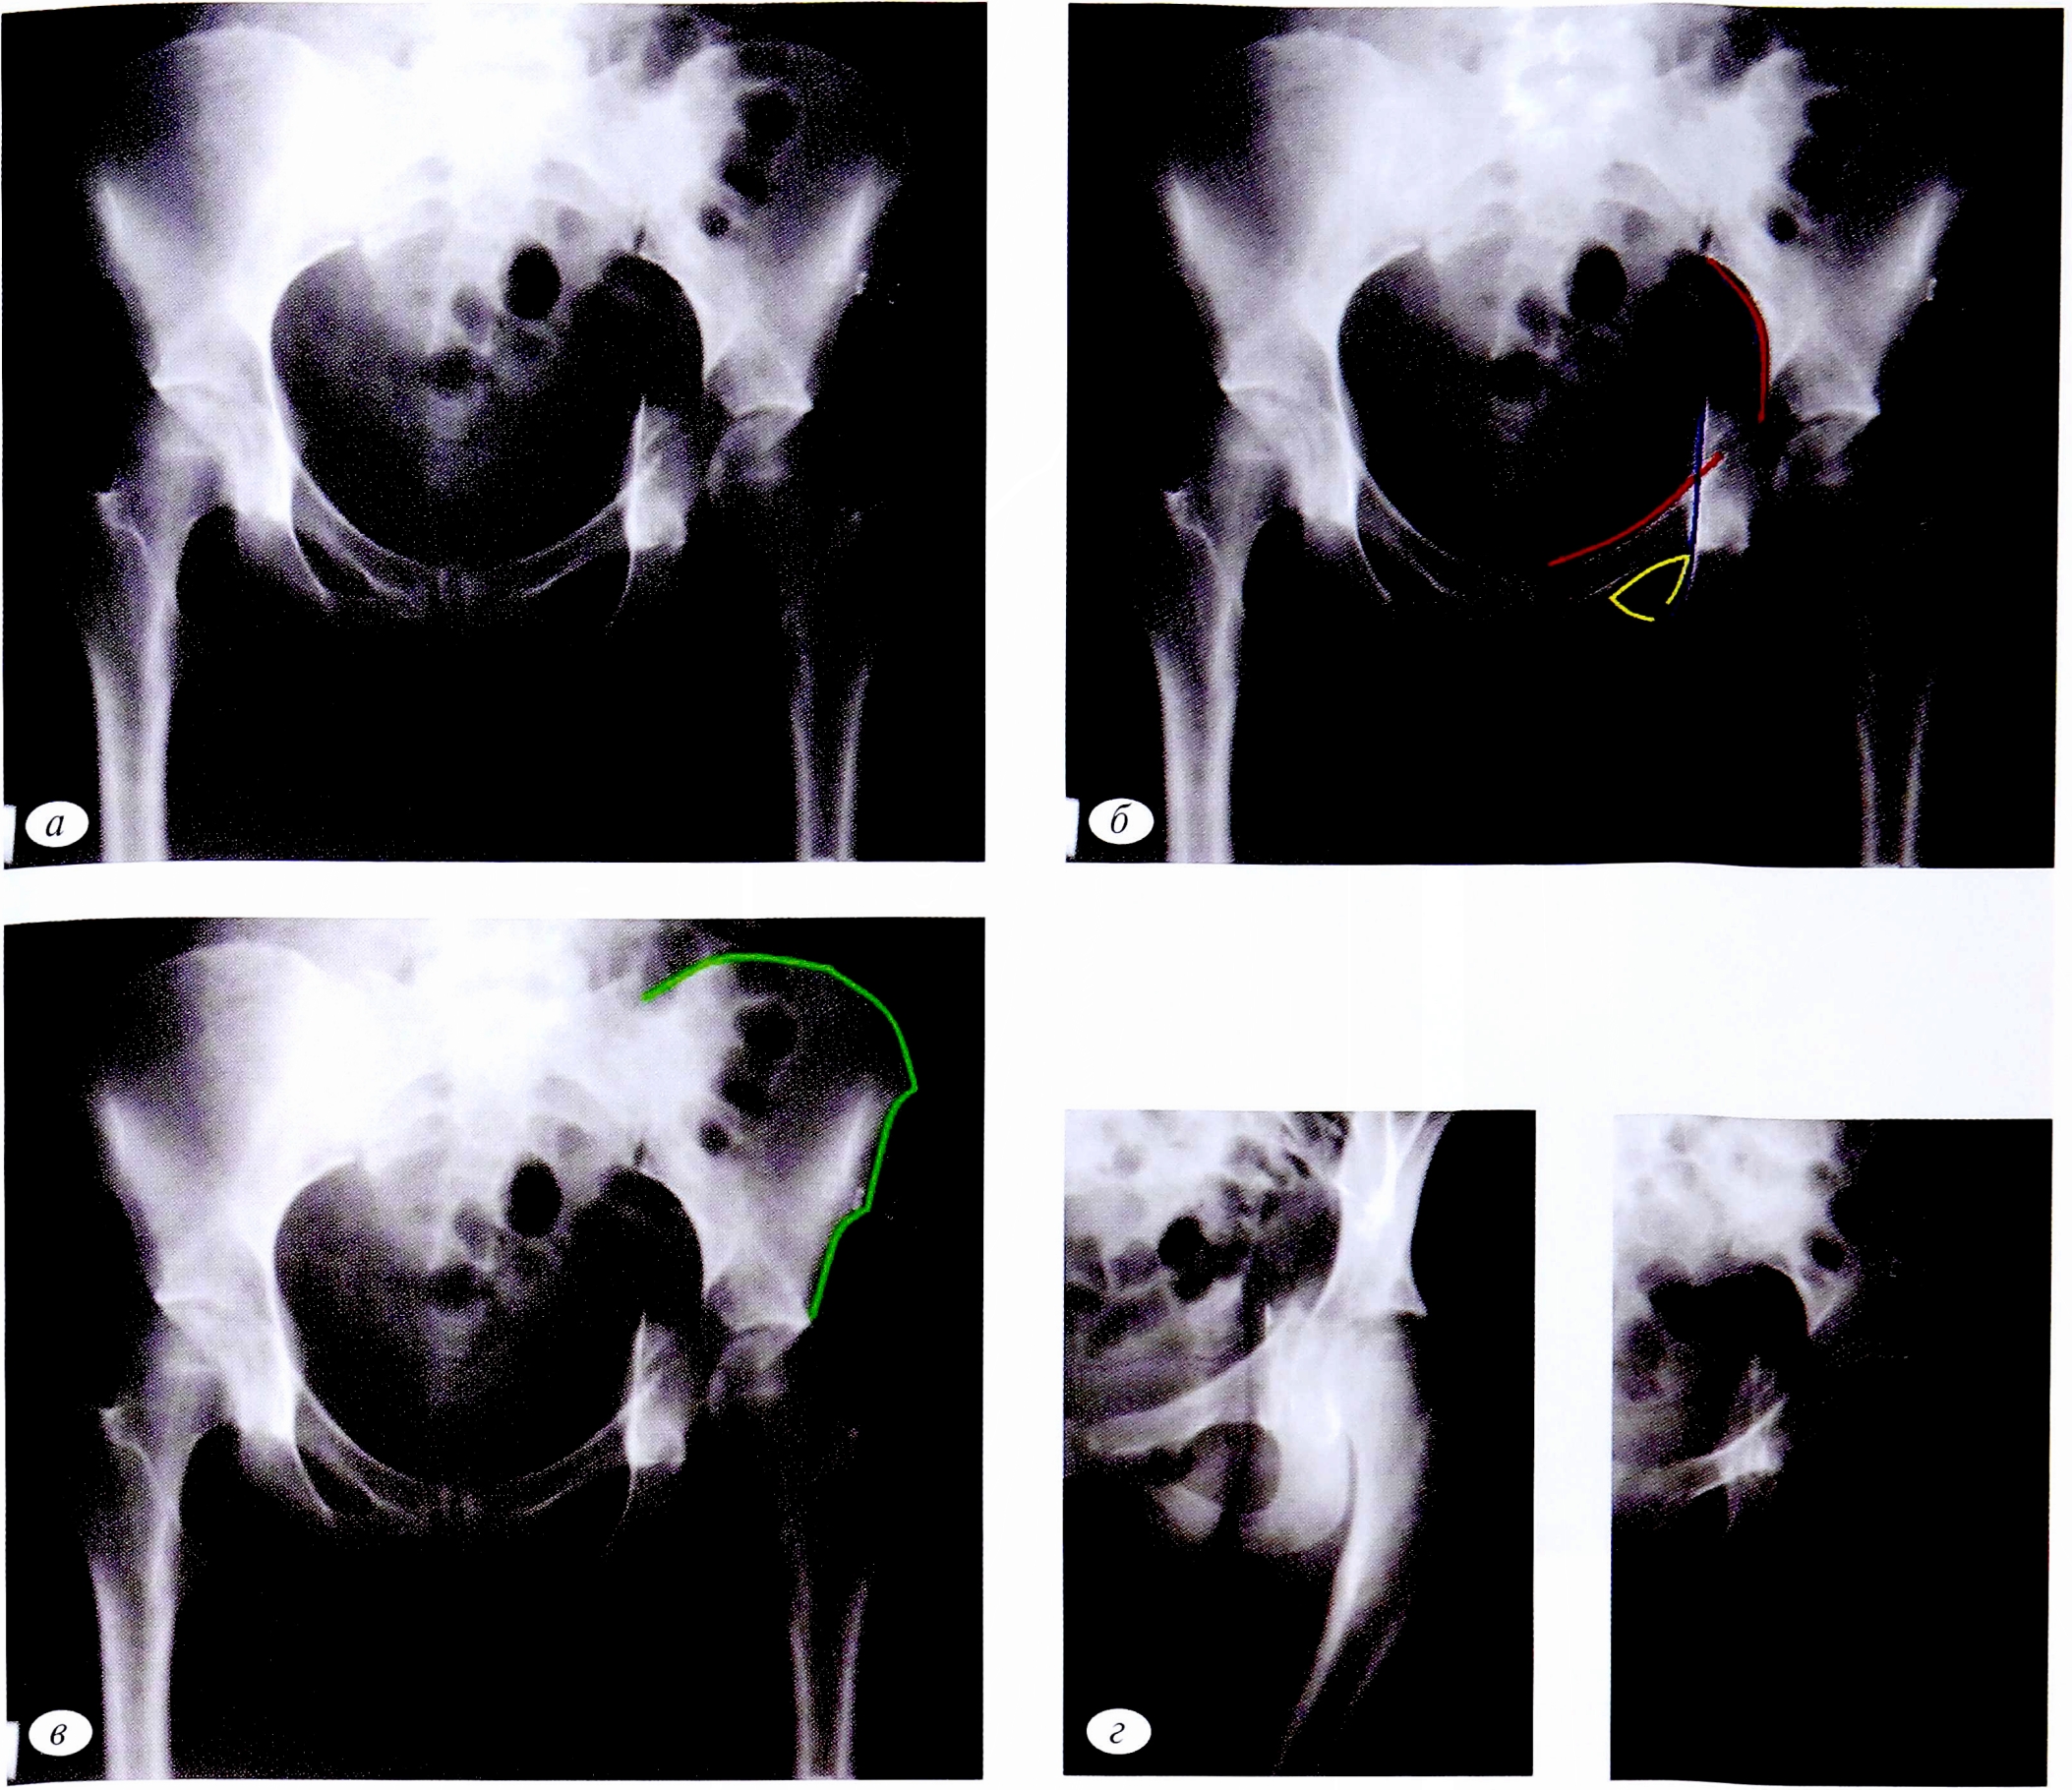

На обзорной рентгенограмме, представленной на рис. 2, а, из основных референтных линий определяется целостность контуров запирательного отверстия. На первом этапе можно исключить переломы элементов вертлужной впадины, формирующих запирательное отверстие (участки лонной и седалищной костей ниже уровня фигуры слезы). К таким переломам относятся перелом передней колонны, задней колонны, задней колонны, ассоциированный с переломом задней стенки, Т-образный перелом, перелом передней колонны, ассоциированный с задним полу- поперечным, двухколонный перелом (см. рис. 2, б).

При дальнейшем анализе рентгенограммы с учетом нарушенных референтных линий возможно определение топической локализации перелома. Наличие отдельного фрагмента задней стенки позволяет исключить те переломы, при которых он не определяется, а именно: перелом передней стенки, поперечный перелом (см. рис. 2, в).

Повреждение как подвздошно-гребешковой, так и подвздошно-седалищной линии свидетельствует о повреждении обеих колонн вертлужной впадины, что дает возможность исключить изолированный перелом задней стенки. Таким образом, методом исключения диагностирован поперечный перелом, ассоциированный с переломом задней стенки (см. рис. 2, г).

С помощью прицельных рентгенограмм в косых проекциях установленный диагноз подтверждается (см. рис. 2, д, е). На рентгенограмме в запирательной проекции определяется отдельный фрагмент задней стенки. Перелом как передней, так и задней колонны расположен в одной плоскости, проходящей через свод вертлужной впадины (транстектальный перелом), что также свидетельствует о поперечно-ориентированном переломе. Сочетание повреждений вертлужной впадины позволяет выявить сложный многоплоскостной характер перелома.

Рис. 2. Пациент №2. а — обзорная рентгенография таза при поступлении; б — первый этап определения перелома; в — второй этап диагностики перелома; г — установление поперечного перелома, ассоциированного с задней стенкой; д, е — верификация поперечного перелома, ассоциированного с задней стенкой, с помощью прицельных рентгенограмм.

Fig. 2. Patient №2. а — observational X-rays of the pelvis at admission; б — the first stage of fracture detection; в — the second stage of fracture diagnosis; г — transverse fracture associated with the back wall detection; d, e — verification of the transverse fracture associated with the back wall with sighting X-rays.